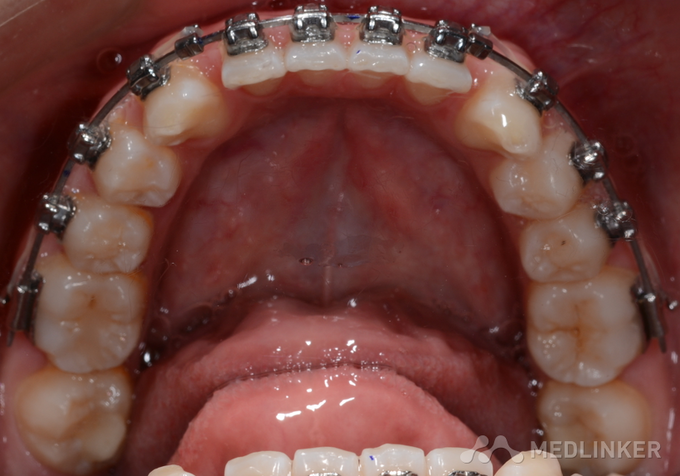

操作滑动关闭间隙技术需严格遵循规范步骤,确保治疗效果和安全性。准备阶段:拔牙后需等待2-3周,待拔牙窝初步愈合、无明显炎症后开始治疗,同时需全面评估口腔卫生状况,若有牙龈炎、牙周炎需先进行牙周治疗,控制炎症后再关闭间隙;支抗准备是关键,根据患者错颌类型选择支抗方式,如常规支抗可使用横腭杆、Nance弓,强支抗则需植入种植支抗钉(微种植体),防止后牙前移过多。弓丝选择与弯制:早期使用镍钛圆丝(0.014-0.018英寸)排齐牙齿,解除扭转和拥挤,待牙列完全排齐后换用不锈钢方丝(0.018×0.018英寸或0.022×0.028英寸),方丝的刚性更强,能更好地控制牙齿移动方向;弓丝需弯制“泪滴曲”或“Omega曲”,曲的位置距后牙托槽约1mm,确保牵引力通过牙齿阻抗中心,避免倾斜移动。托槽粘接:前牙托槽粘接于牙冠中心,后牙支抗牙托槽略靠龈方(距牙合面边缘4mm),防止弓丝受力后变形;托槽槽沟需与弓丝紧密贴合,减少摩擦力。结扎与加力:使用结扎丝或自锁托槽的滑动机制将弓丝固定于托槽,确保弓丝完全入槽;牵引装置可选择橡皮链(持续力)或螺旋弹簧(间歇力),橡皮链需每4-6周更换一次,避免力量衰减;加力时需测量间隙剩余量,按1mm/月的速度关闭间隙,避免加力过急导致牙根吸收。复诊调整:每4-6周复诊一次,检查牙齿移动情况、弓丝是否变形、牵引力是否有效,拍摄根尖片观察牙根位置和牙槽骨改建情况,必要时调整弓丝形态或加力方式。